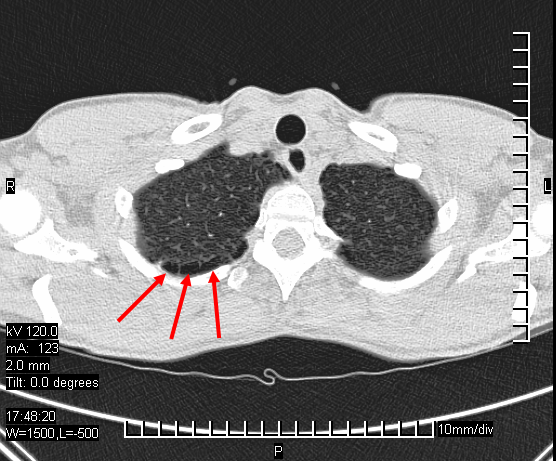

Bei der Suche nach der Ursache wurde auf einem Röntgenbild der Lunge ein etwa 5 cm großer Hohlraum im linken oberen Lungenlappen festgestellt, der am ehesten einem Lungenabszess entsprach. Das Blutbild war unauffällig, MRT des Gehirns und der Wirbelsäule erfolgte, zeigte jedoch keine Abnormalitäten (ein weiteres CT/MRT wäre hilfreich gewesen).

Runder Hohlraum im linken oberen Lungenlappen.